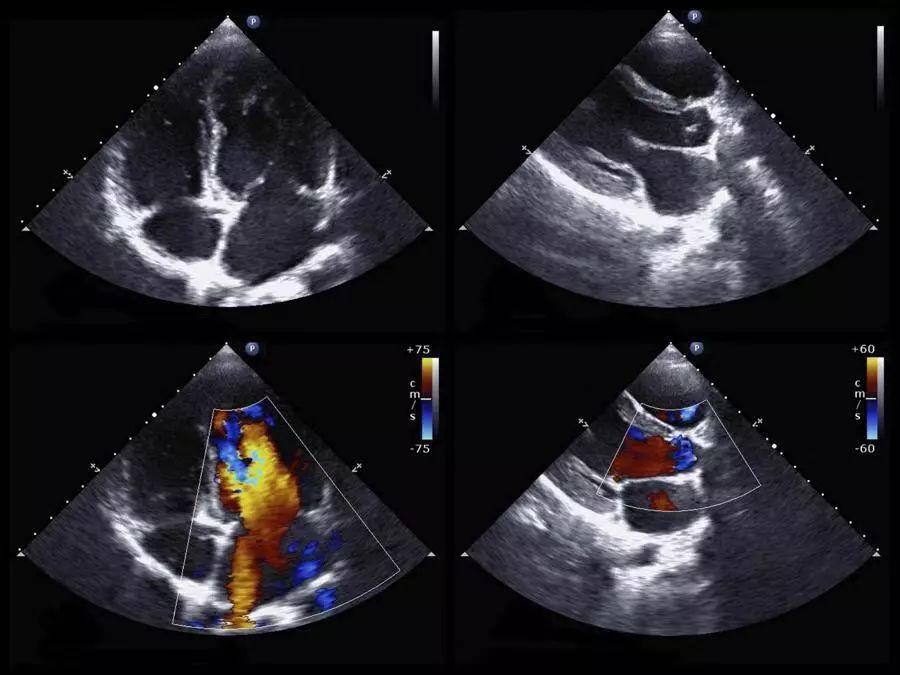

二尖瓣、三尖瓣、主动脉瓣少量返流

单纯瓣膜少量返流没有太大的临床意义,往往是瓣膜老化的表现。你想啊,不管家里卧室门还是汽车门,用了十年、几十年了,透点风是不是很正常啊。